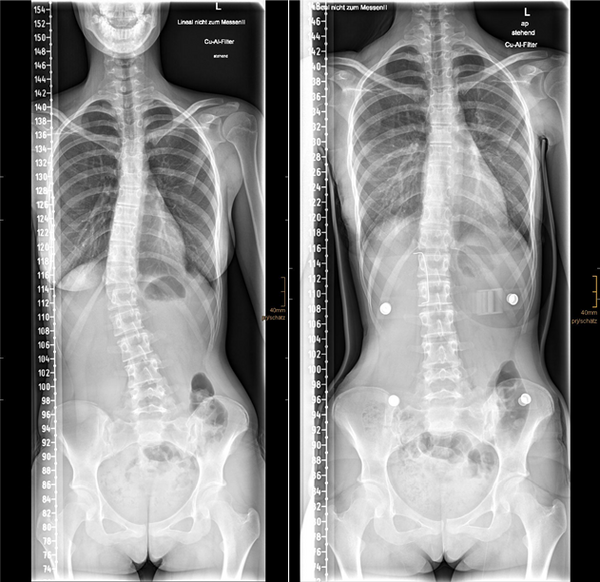

Skoliose_Spondylodese

Bild 2: Ein Beispiel für die operative Behandlung einer Skoliose mit einer Spondylodese (Versteifungsoperation). Die Krümmung wird mit dem Implantat korrigiert und die Wirbelsäule stabilisiert.